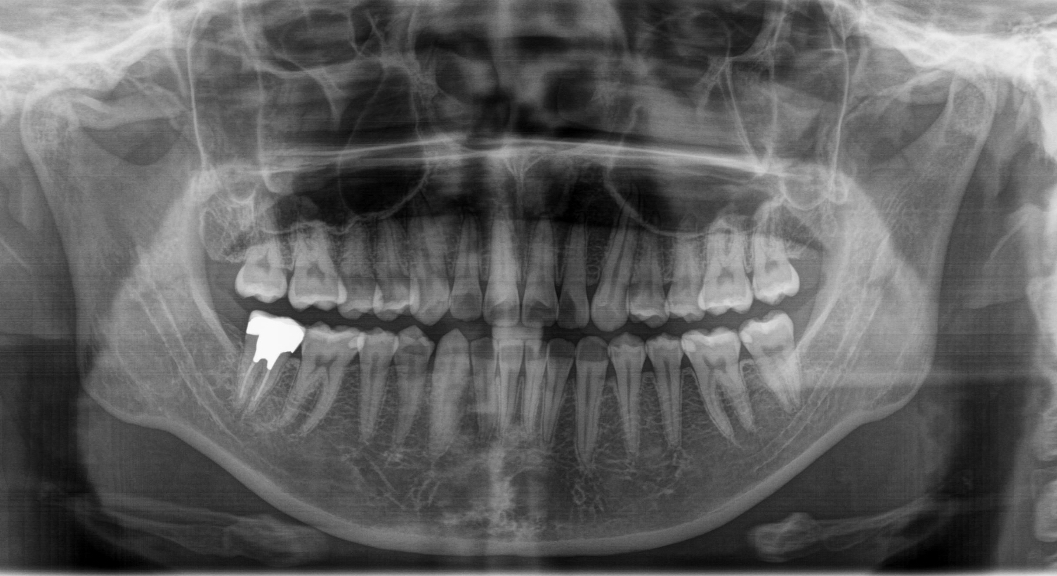

お口全体のレントゲン(パノラマX線写真)と一部を詳しく写すレントゲン(咬翼法)の2種類を撮影いたします。

パノラマX線撮影は、全体の把握に優れます(+顎関節・親知らずなど)

パノラマX線写真